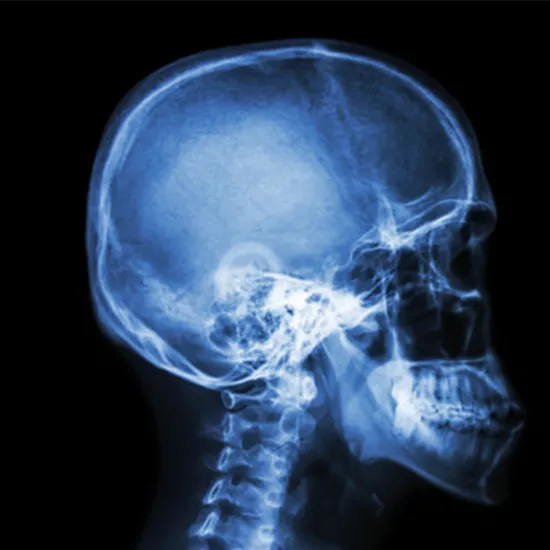

X-Ray Head & Neck AP/Lateral

Book X-Ray Head & Neck AP/Lateral Appointment Online Near me at the best price in Delhi/NCR from Ganesh Diagnostic. NABL & NABH Accredited Diagnostic centre and Pathology lab in Delhi offering a wide range of Radiology & Pathology tests. Get Free Ambulance & Free Home Sample collection. 24X7 Hour Open. Call Now at 011-47-444-444 to Book your X-Ray Head & Neck AP/Lateral at 50% Discount.

What is an X-ray Neck AP LAT View Test?

An X-ray of the cervical spine shows the bones in the back of the neck (7 cervical vertebrae), the first vertebrae of the thoracic spine, and the spaces between the vertebrae. It can be used to find out what is causing neck pain, fractures or broken bones, arthritis, spondylosis, degeneration of the discs, and tumors.